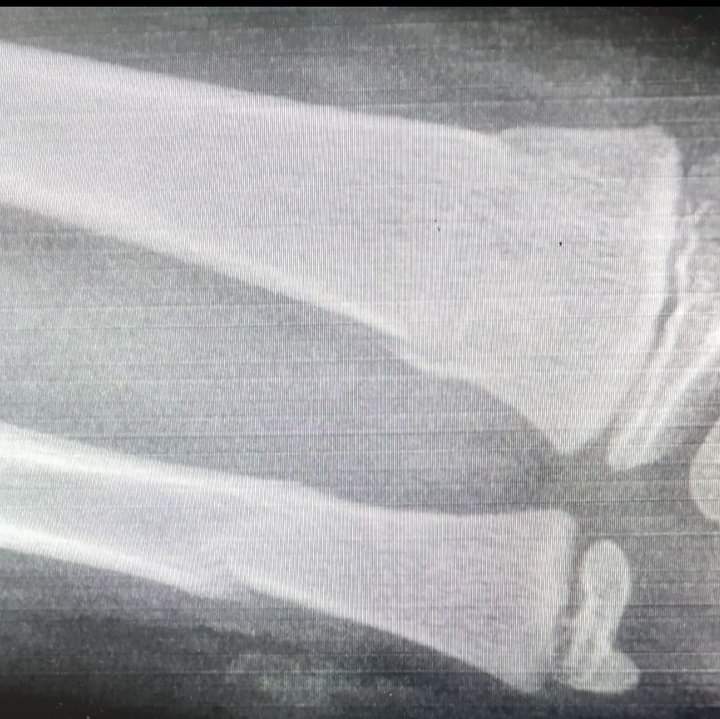

تعرض طفل يوم امس الى هجوم من قبل كلب مفترس في منطقة اسكان المغاريب / 4 كلم شمال مدينة السلط

وقالت مصادر مطلعة ان الطفل قد اصيب بكسرين نتيجة قوة العضة وانه قد اسعف الى المستشفى لتلقي العلاج اللازم

جدير بالذكر ان هذه هي الحاله الثانيه التي تحدث في منطقة المغاريب وبنفس اليوم